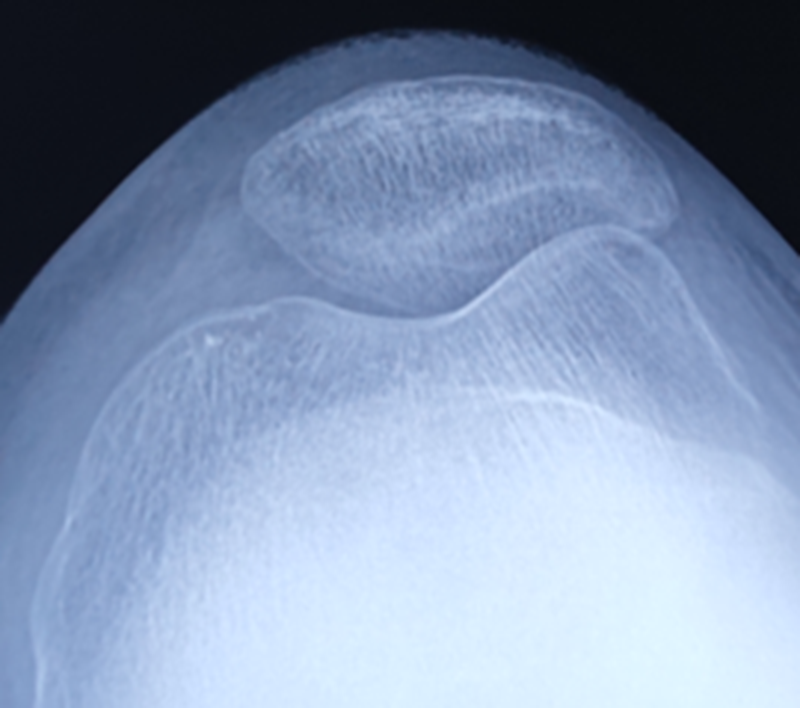

术前X线

术后X线